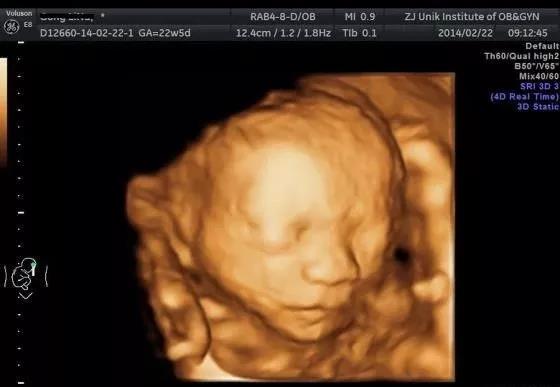

三维超声顾名思义,就是可以看到3D立体的图像。医生在检查时可以直观清晰地看到各个结构形态,还能看到更多不同切面,提高了对胎儿畸形,特别是头面部畸形的诊断。四维超声比三维再多加了一个时间上的维度,就好比3D录像,可以动态观察特定部位的变化,相对来说会更清楚,提供更多诊断信息。

三维和四维彩超会比二维看的更清晰,在孕中晚期做系统大排畸检查或一些特殊情况检查时,医生通常会建议做三维和四维彩超。在孕早期检查中,二维超声的检查效果与三维不相上下,这时一般做普通的B超,如有特殊情况医生才会建议进一步检查。

此时胎儿的复杂器官如心脏和大脑已经发育好,是进行系统性超声检查排查畸形的最佳时期。检查内容包括胎方位、胎心搏动、胎儿生物学测量,对胎儿的大脑、颜面部、颈部、胸部、心脏、膈肌、腹部、脊柱、四肢全面观察,还包括胎盘、脐带、羊水量的检查,筛查六大致死性畸形和各主要器官的畸形。这是产前超声检查中最重要的一次,一般需要30~45min,各位孕妈需要提前预约好,以免错过最佳时期。